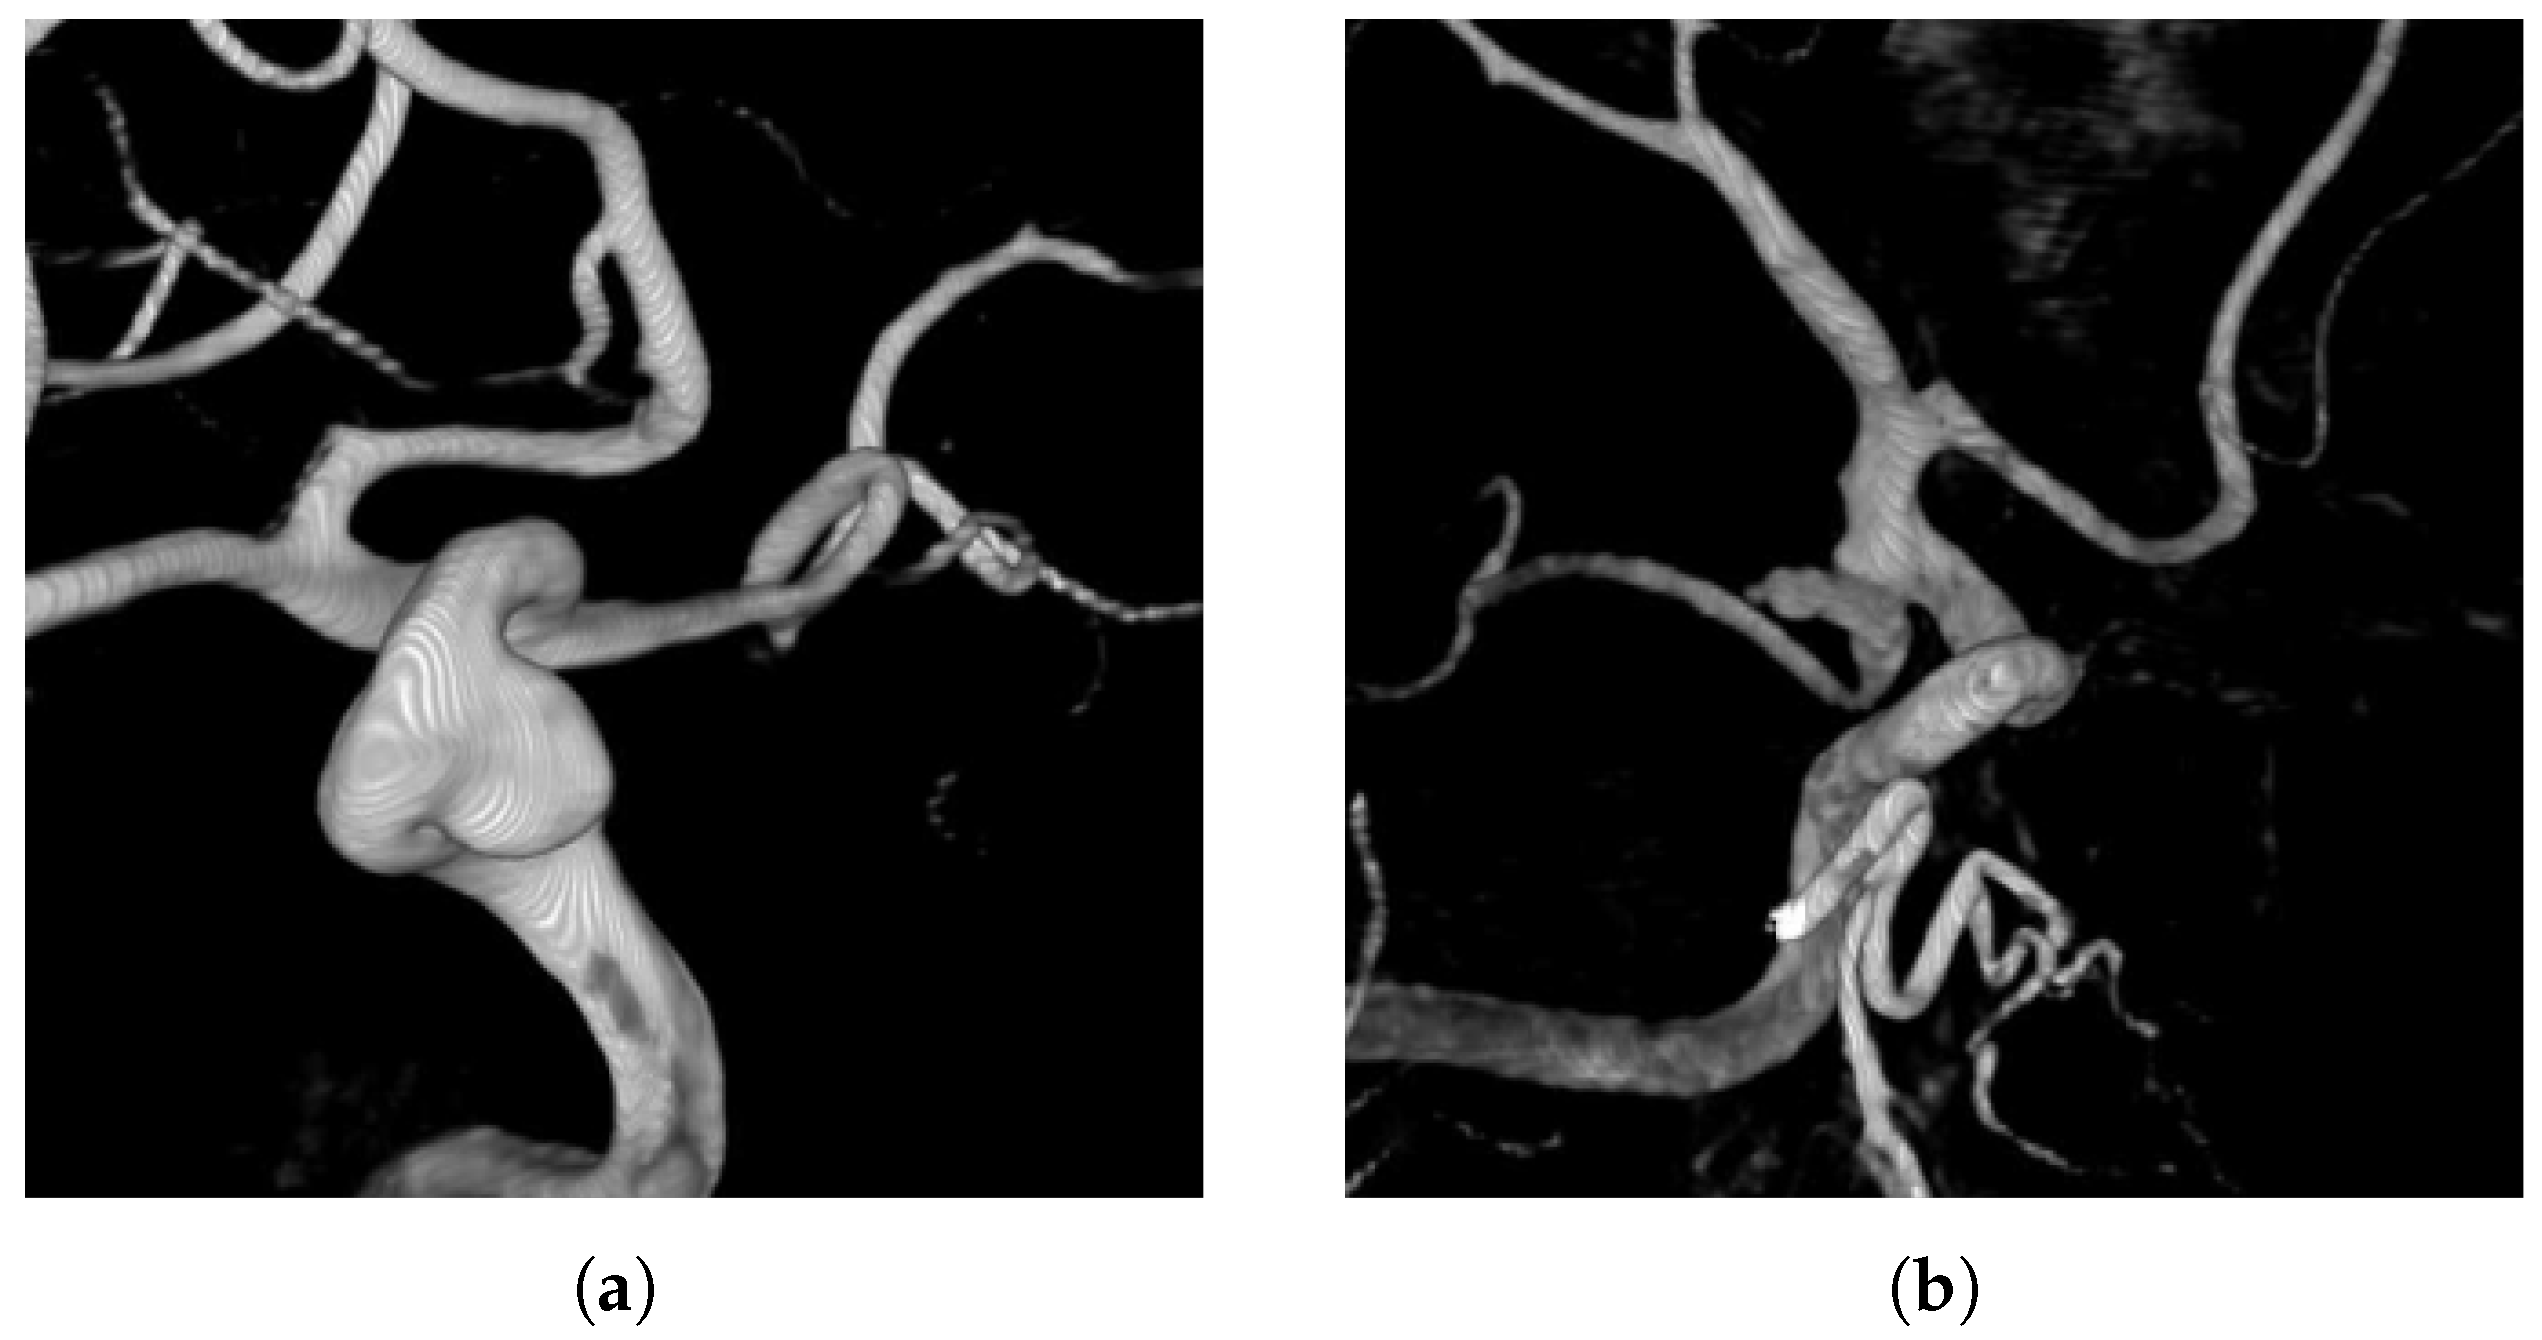

The dataset used consists of DSA images of intracranial aneurysms from the First Affiliated Hospital of Zhejiang University School of Medicine, involving 120 patients who were admitted in 2023. After screening, a total of 867 images were obtained. These images cover the various locations and morphologies of aneurysms. In the annotation process, we collaborated with professional neuro-interventional doctors. With the help of the LabelImg tool, the aneurysm regions were accurately marked with rectangular bounding boxes. The aneurysm lesions are classified into two types: sidewall aneurysms and bifurcation aneurysms, as shown in Figure 7. The former are mostly located on one side of the arterial wall, while the latter are commonly found at vascular bifurcations. Bifurcation aneurysms have a complex shape, making them more difficult to identify. Classifying and annotating these two types of aneurysms helps to improve the recognition ability of the model.

Figure 7. DSA images of sidewall-type and bifurcation-type aneurysms. (a) Sidewall aneurysms. (b) Bifurcation aneurysms.